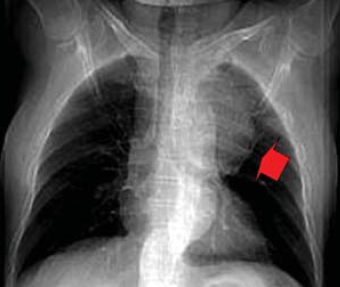

8. ábra.

PAU a distalis aortaíven. Az álaneurysma csaknem perforálja a mellkasfalat.